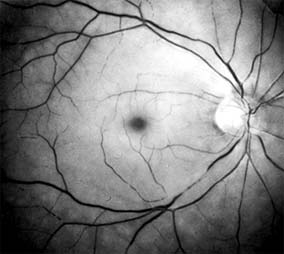

Diabetic retinopathy is a progressive microangiopathy characterized by small vessel damage and occlusion. The earliest pathologic changes are thickening of the capillary endothelial basement membrane and reduction of the number of pericytes. Background diabetic retinopathy is a clinical reflection of the hyperpermeability and incompetence of involved vessels. The capillaries develop tiny dot-like outpouchings called microaneurysms, while the retinal veins become dilated and tortuous (Figure 10-20).

Figure 10-20

Figure 10-20: Background diabetic retinopathy with abundant macular exudate (open arrow), micro-aneurysms (small arrow), and intraretinal hemorrhage (large arrow).